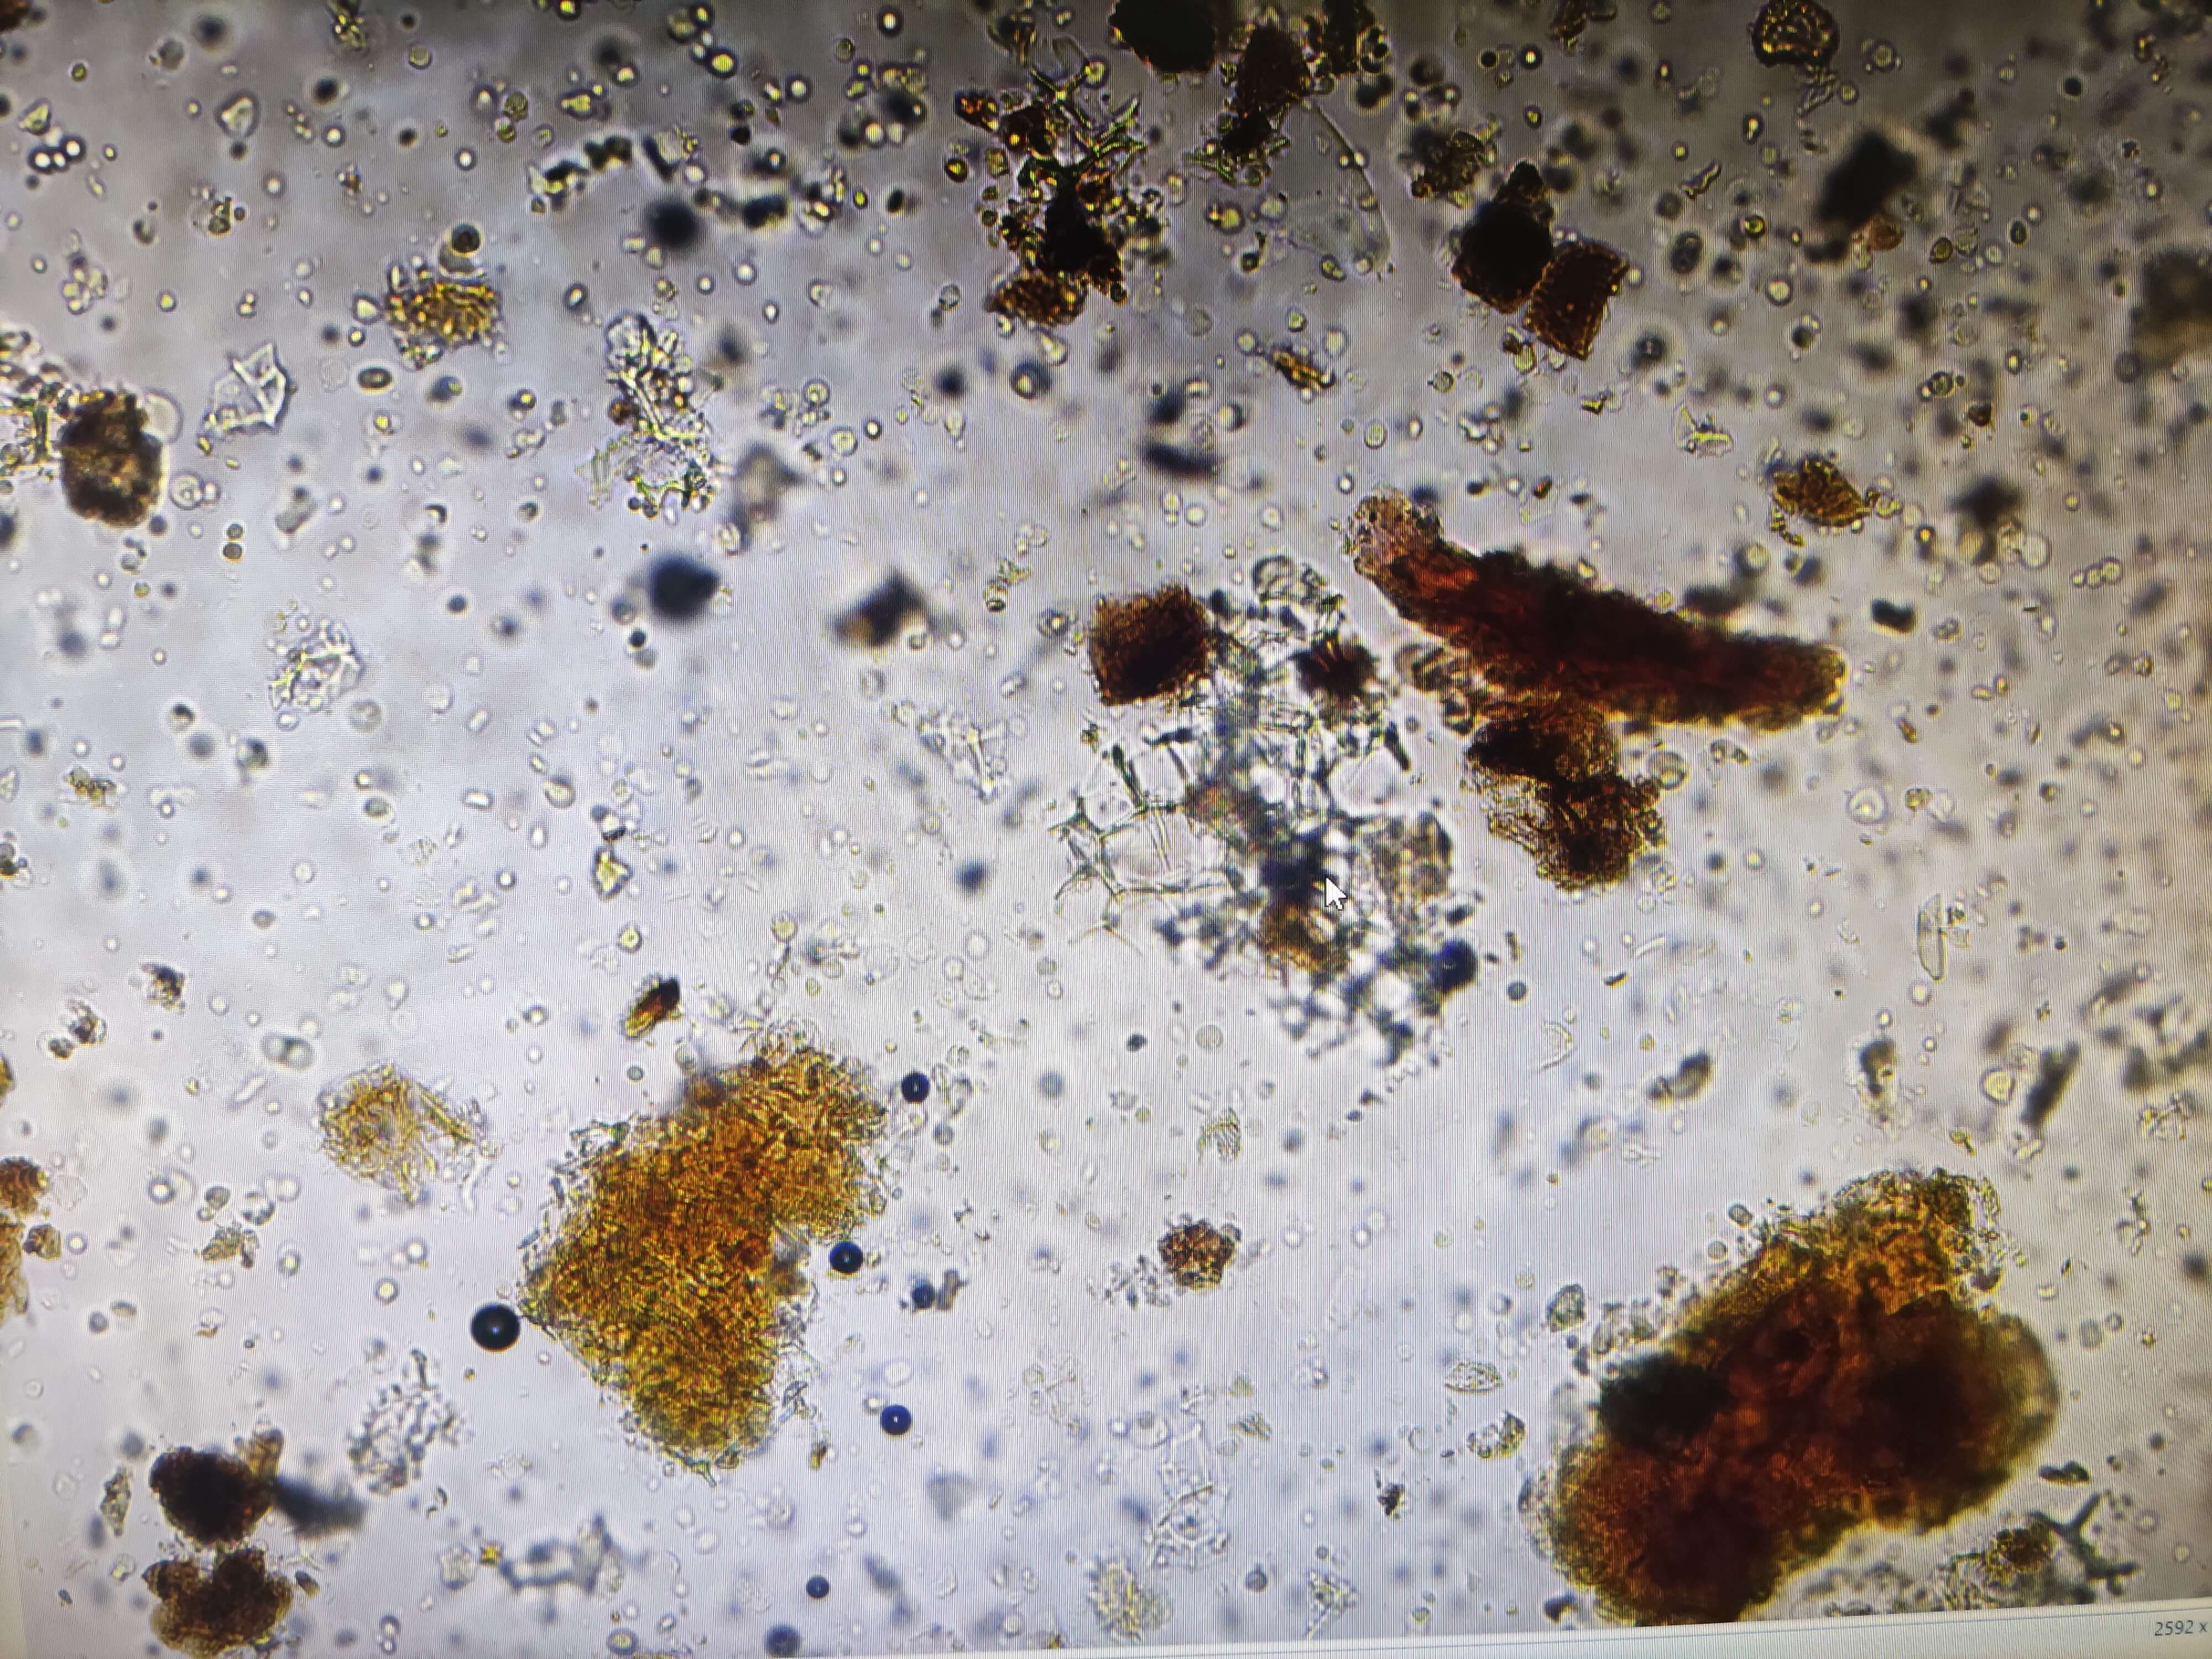

甘草

| 甘草 |

|---|

| 【参考标准】 《中国药典》2020年版一部 |

| 【显微鉴别】 粉末淡棕黄色。纤维成束,直径8~14μm,壁厚,微木化,周围薄壁细胞含草酸钙方晶,形成晶纤维。草酸钙方晶多见。具缘纹孔导管较大,稀有网纹导管。木栓细胞红棕色,多角形,微木化。 |

| 【显微重点】 草酸钙方晶;晶纤维。 |

| 【图谱来源】 《中药成方制剂显微图典》 |